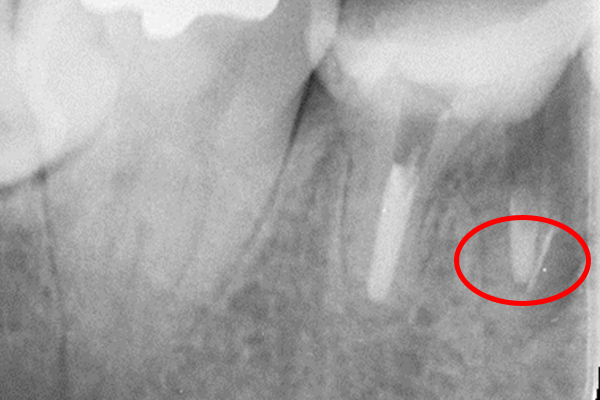

更に、拡大すると歯根破折に加え、器具の破折片も確認できる。

| 治療費 | 破折ファイルの除去費:16,500円 |

| 治療内容 | 破折ファイルの除去 |

| 治療のリスク | 抜歯の可能性 |